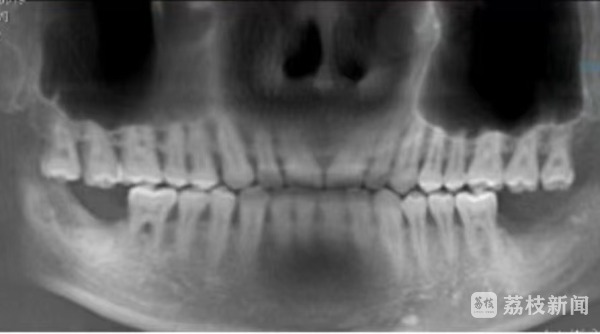

今年3月6日,顾先生(化名)在南京贝鹤雅康口腔医院购买了两颗诺贝尔active种植牙,连同其他费用共计17500元,当时,顾先生缴纳了7000元定金,医院也承诺可以立刻手术。